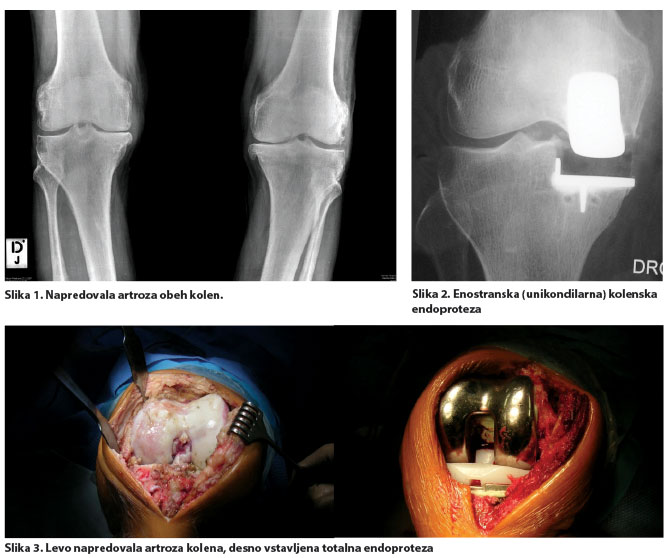

V napredovalih stadijih artroze, ko je kakovost življenja pomembno okrnjena zaradi bolečin v sklepu, slabe gibljivosti oziroma deformacije, in ko konservativni ukrepi niso več učinkoviti, se odločimo za vstavitev kolenske endoproteze. Če gre za prizadetost samo ene strani kolena, lahko vstavimo delno oziroma enostransko kolensko endoprotezo (slika 2.), v primeru razširjene prizadetosti sklepa pa vstavimo totalno kolensko endoprotezo.

Totalna endoproteza kolena je operativna metoda, pri kateri obe sklepni površini obolelega sklepa nadomestimo z umetno protezo, ki jo čvrsto fiksiramo v kost. Tako obnovimo gibljivost sklepa ter funkcijo mišic, ligamentov in drugih mehkotkivnih struktur, ki nadzirajo sklep.

Umetni kolenski sklep je sestavljen iz femoralnega (stegneničnega) in tibialnega (goleničnega) dela, ki sta kovinska, med njima pa je polietilenska ploščica. Oba kovinska dela sta čvrsto fiksirana na kost s kostnim cementom, pri mlajših s čvrsto kostjo se lahko odločimo tudi za brezcementno učvrstitev. Občasno je treba vstaviti še tretji del na pogačico.